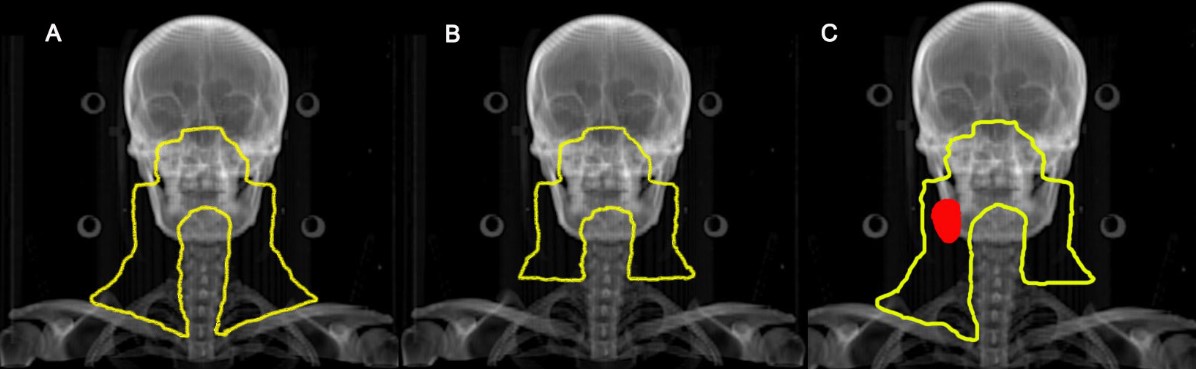

鼻咽癌預防照射范圍示意圖

A:對照組:無論有無淋巴結轉移均行全頸部預防照射

B:試驗組:無頸部淋巴結轉移,雙側頸部行上半頸部照射

C:試驗組:單側淋巴結轉移(紅色區域),淋巴結陰性側行上半頸部照射